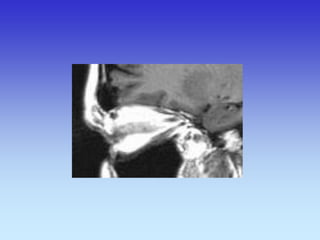

HIPOFIZA

Normalno

Tvorba selarnog područja